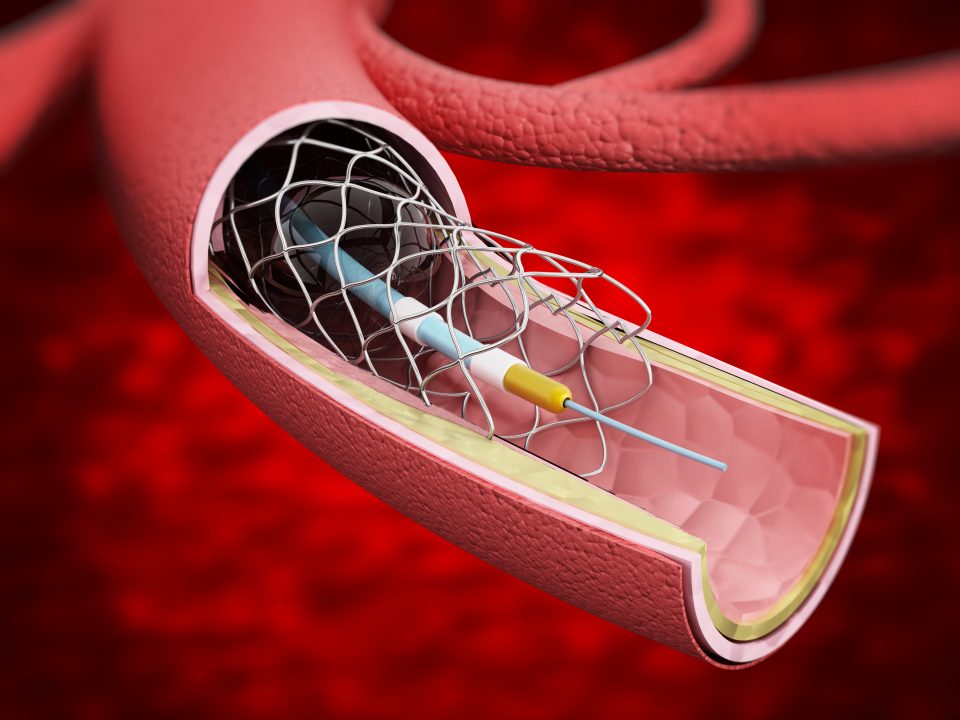

Despite successful percutaneous coronary intervention (PCI), symptomatic patients without residual ischemia improved ...

“Angiography” and “angioplasty” may sound like intimidating medical jargon to a patient undergoing a procedure ...